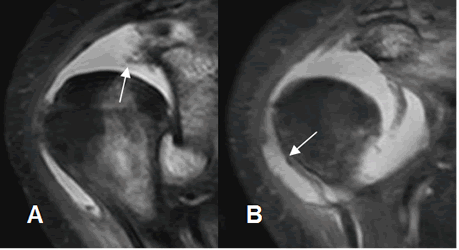

Fig 153. Ruptura del biceps.

A: RM coronal en STIR: Ruptura retraída de la cabeza larga del biceps, con el extremo en la corredera bicipital.

B: RM axial en FFE. Corredera bicipital vacía y ocupada por líquido.